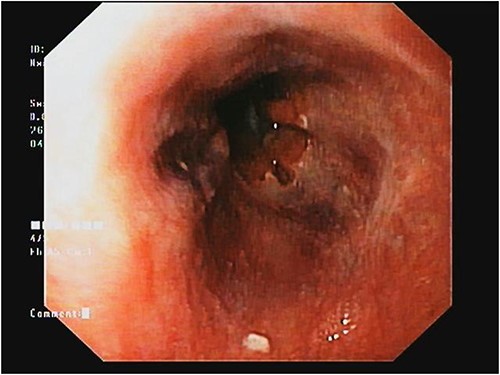

The patient’s complete blood count indicated pancytopenia, while liver function tests showed no significant abnormalities. Upper gastrointestinal endoscopy showed the presence of small esophageal varices and severe portal hypertensive gastropathy (Fig. 3).